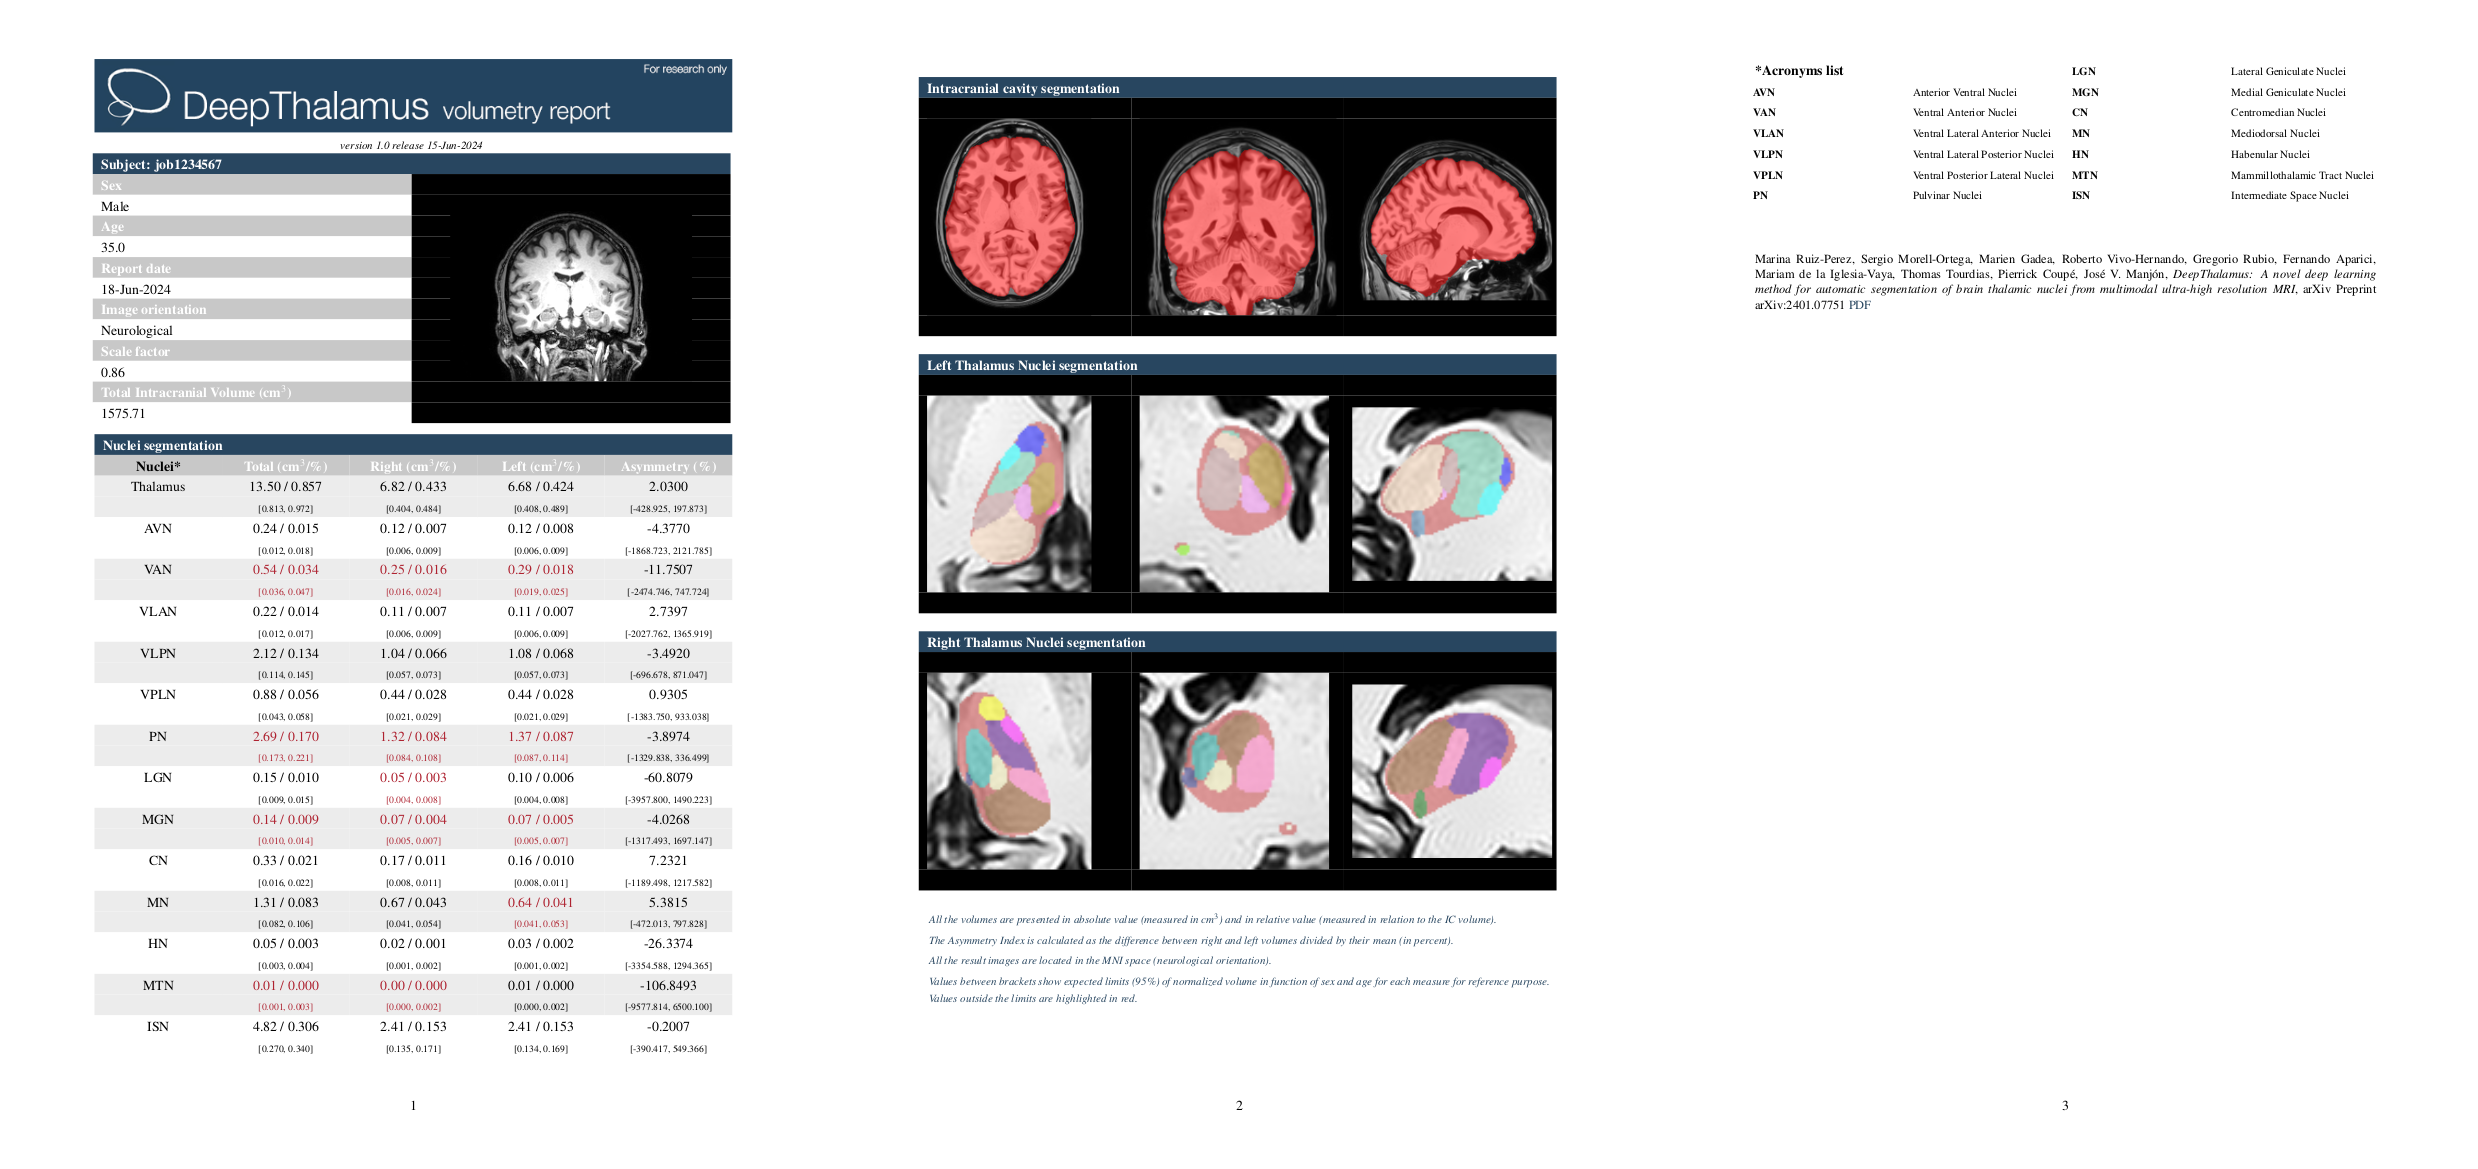

Once the process is completed, you will be notified by email and you will be able to download a package that includes some image files and two reports (CSV and PDF) with all the volumes estimated from the segmentations. As you can see in the figure below, the PDF includes the patient information, the volume of the whole thalamus and the nuclei of each hemisphere, as well as the asymmetry indices. Finally, it also includes snapshots of the result of the segmentations as a quality control.

Marina Ruiz-Perez, Sergio Morell-Ortega, Marien Gadea, Roberto Vivo-Hernando, Gregorio Rubio, Fernando Aparici, Mariam de la Iglesia-Vaya, Thomas Tourdias, Pierrick Coupé, José V. Manjón. DeepThalamus: A novel deep learning method for automatic segmentation of brain thalamic nuclei from multimodal ultra-high resolution MRI. arXiv Preprint arXiv:2401.07751 PDF